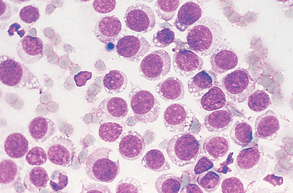

Suppurative (purulent) inflammation (Fig. 9-28) is characterized by the presence of large numbers of neutrophils, usually greater than 85% of the total nucleated cell count. When significant numbers of macrophages are present (greater than 15%), the sample is classified as granulomatous or pyogranulomatous (Fig. 9-29). Fungal and parasitic infections often manifest with this presentation. The presence of greater than 10% of eosinophils along with increased neutrophils indicates an eosinophilic inflammation (Fig. 9-30). This is usually found with parasitic infection but may also be present in some neoplastic disorders.

Figure 9-28 Suppurative inflammation as evidenced by the large number of neutrophils. Note the presence of karyorrhexis in the center cell. (From Raskin RE, Meyer DJ: Atlas of canine and feline cytology, St Louis, 2001, Saunders.)